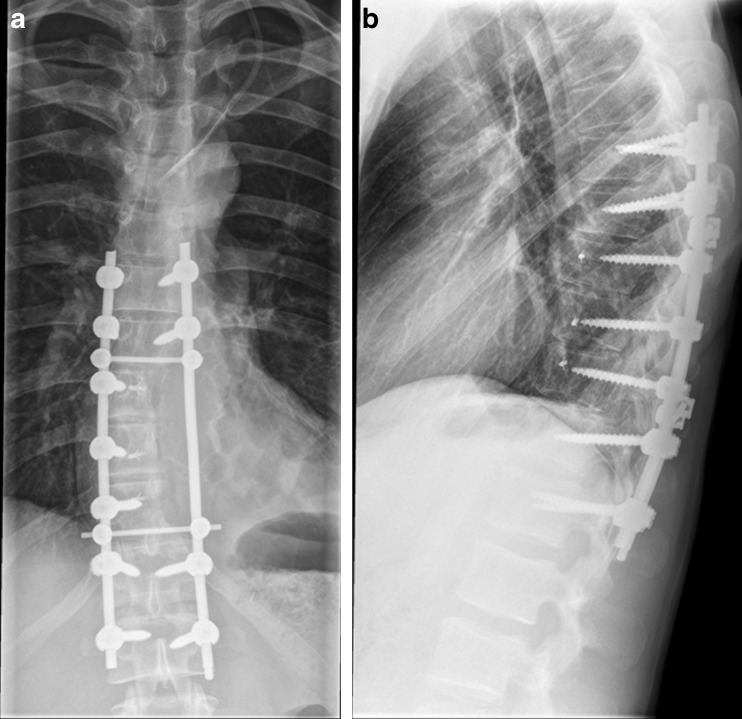

Fig. 2.

a, b Anteroposterior and lateral plain radiographs of the thoracic spine 3 months following wide resection of a Ewing’s sarcoma with hemicorporectomy and spinal fusion